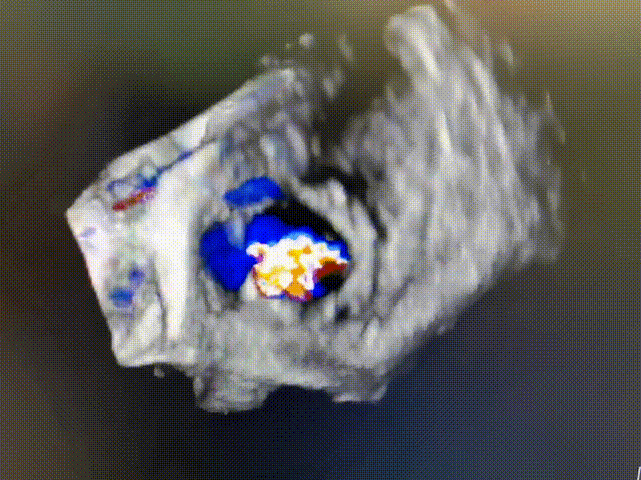

CTA数据显示:患者三尖瓣位可见“C”型人工成形瓣环(28mm Edwards MC3),成形环内径22.3mm,有效开口面积381.1mm²。

术前食道超声显示:三尖瓣成形术后表现,重度中心性三尖瓣反流,考虑右心室扩大牵拉三尖瓣腱索所致,瓣口面积4.0cm²。

术前三尖瓣重度反流